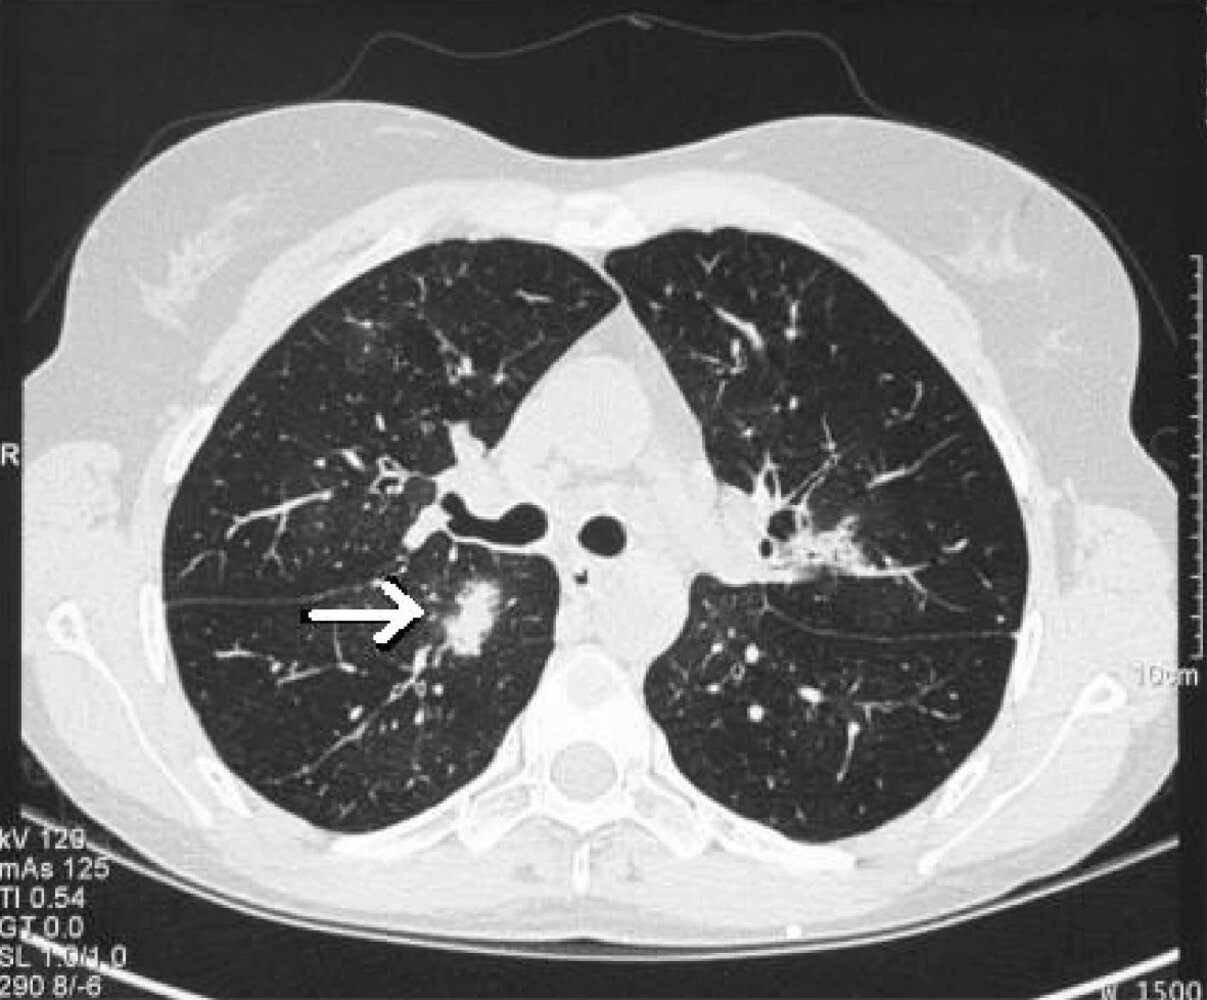

• HRCT chest without contrast (for all suspected cases): [3][8]

• Air crescent sign: a radiolucent crescent around a radiopaque nodule, characteristic of invasive aspergillosis

• Halo sign: hemorrhagic ground glass opacities around nodules

• Multiple nodules